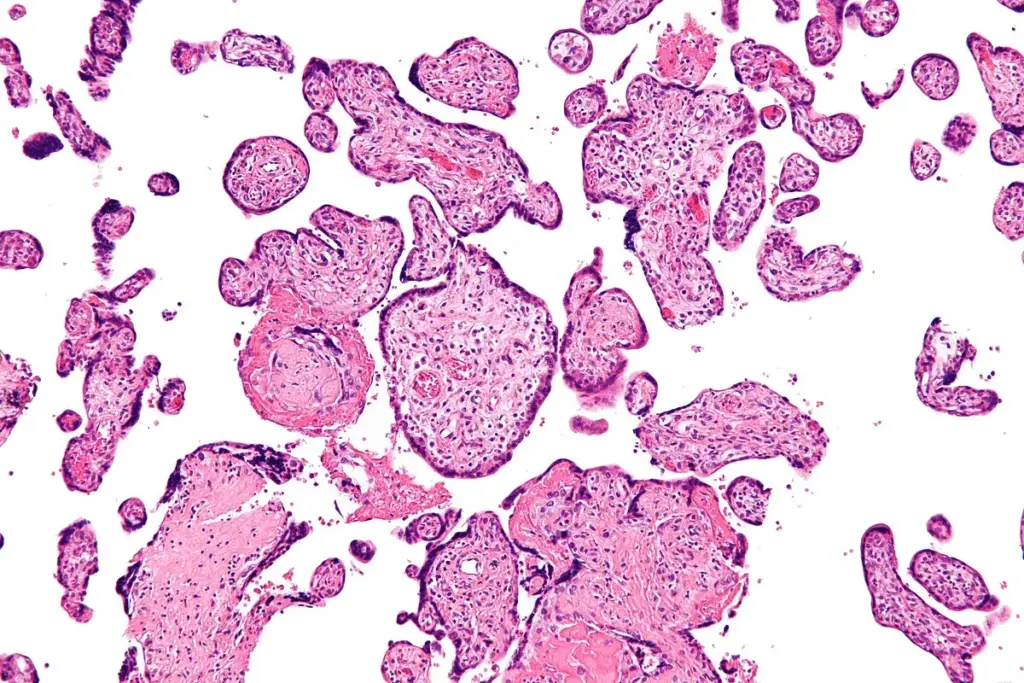

The defining feature of sarcoidosis is the non-caseating granuloma. Unlike the granulomas found in tuberculosis, these do not show central necrosis (decay).

Cellular Composition

These tiny clusters are made up of inflammatory cells, mainly epithelioid histiocytes and multinucleated giant cells, with lymphocytes around them. If granulomas stay in the body, they can damage the normal structure and function of the organ, sometimes causing scarring.